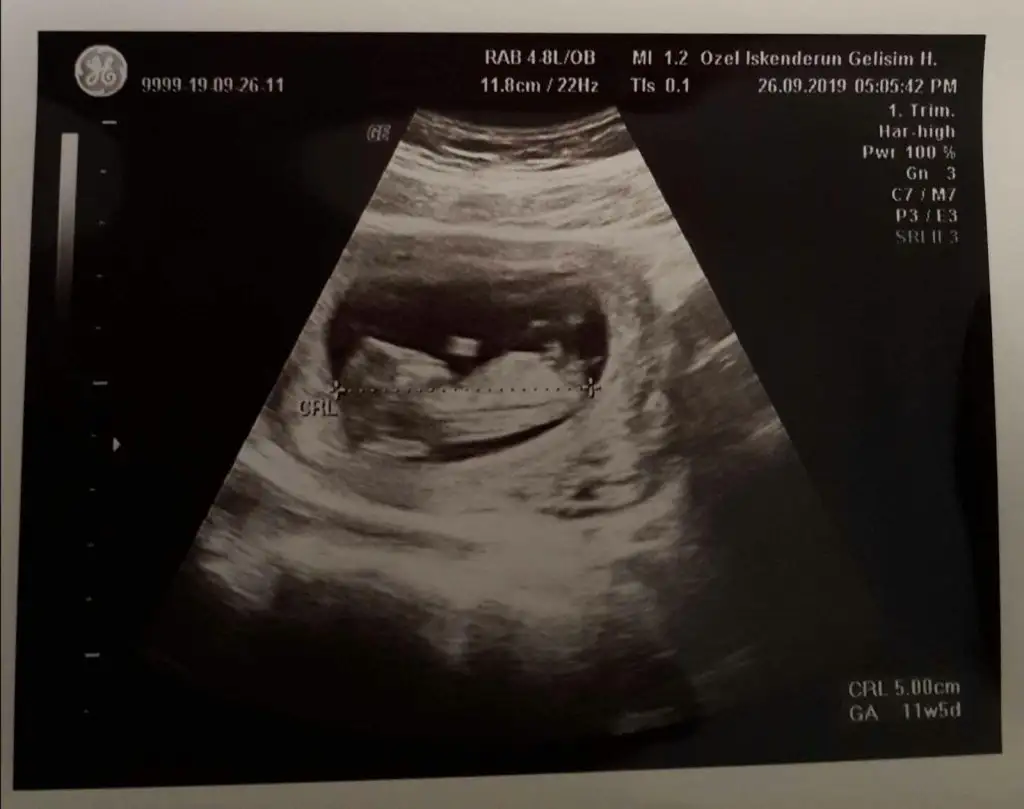

Merhaba kizlr. Devlte gittim anca bu kdarlik gorntu var. Sizce neye benzio. Tam 11 haftlik

Bu da erkek gibiArkadaşlar arkadaşımın bebeğinede bakabilirmisiniz kızmı erkekmi diye 11 hafta 5 günlükEki Görüntüle 2543755